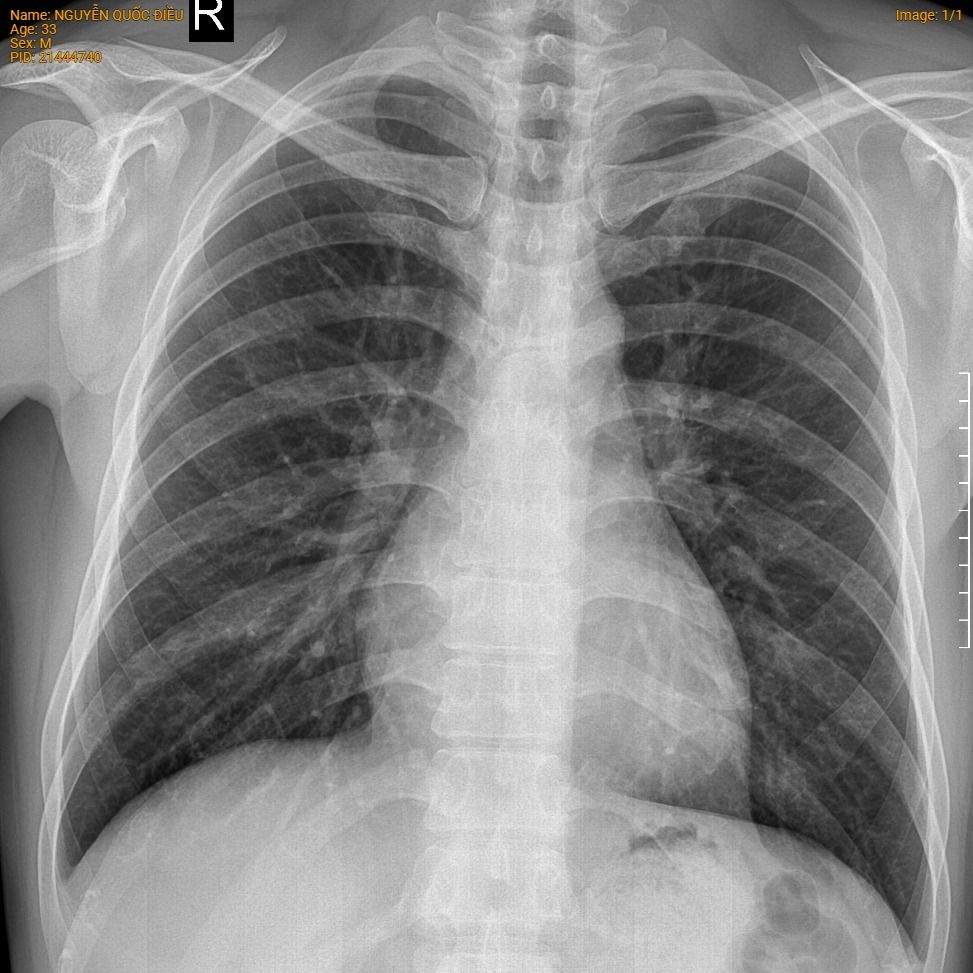

Kết quả dịch vụ: Tim phổi thẳng KTS/KSK (Ko in phim)

- Hình dạng lồng ngực: cân đối

- Phổi phải: đồng nhất. Không thấy dấu hiệu giãn phế quản, phế nang. Không thấy các hình mờ dạng lưới, nốt

- Phổi trái: đồng nhất. Không thấy dấu hiệu giãn phế quản, phế nang. Không thấy các hình mờ dạng lưới, nốt

- Khoang màng phổi hai bên không thấy dấu hiệu tràn dịch, tràn khí

- Khí quản và phế quản gốc: cân đối, không bị đè đẩy

- Trung thất: cân đối, không rộng.

- Bóng tim: hình ảnh bình thường, chỉ số tim ngực trong giới hạn bình thường.

- Cung động mạch chủ: không giãn, bờ đều. Không vôi hóa

- Các xương sườn: hình dạng bình thường, không thấy tiêu xương, đặc xương. Không thấy đường gãy xương

- Phần mềm thành ngực: không thấy cản quang bất thường.

Kết luận

Hình ảnh X quang tim phổi hiện tại không thấy bất thường.